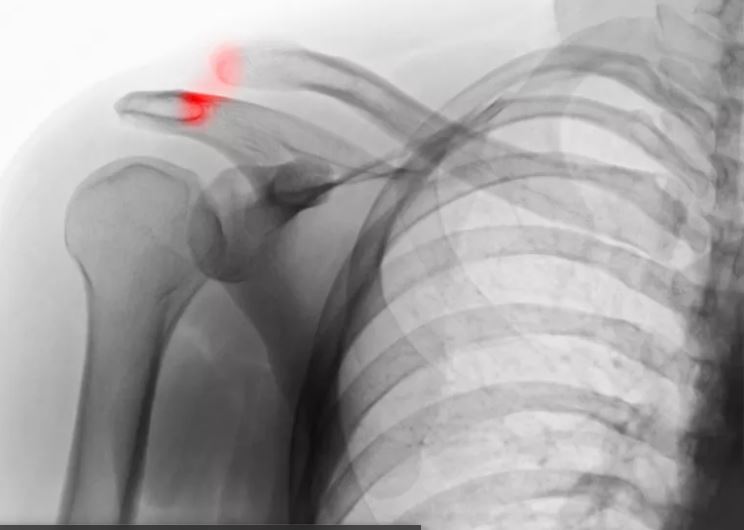

Shoulder Anatomy and Injury

The three bones that form the shoulder joint are secured in place by a number of ligaments, as well as the ever important rotator cuff muscles.

The rotator cuff is comprised of four muscles that combine at the shoulder to form a thick “cuff” over the joint. The rotator cuff has the important job of stabilizing the shoulder as well as elevating and rotating the arm. Each muscle originates on the shoulder blade (scapula) and inserts on the arm bone (humerus). The ball and socket structure is the reason the shoulder is one of the most flexible joints in the body. As a result of this freedom, though, the shoulder is the site of many common injuries. Repetitive overhead motions place the muscles and tendons of the shoulder in a vulnerable position. Therefore, many shoulder injuries occur in people with occupations that require overhead work. Most shoulder injuries can be treated conservatively with rest, ice, mobilization, and physical therapy. However, other shoulder injuries require surgical intervention.